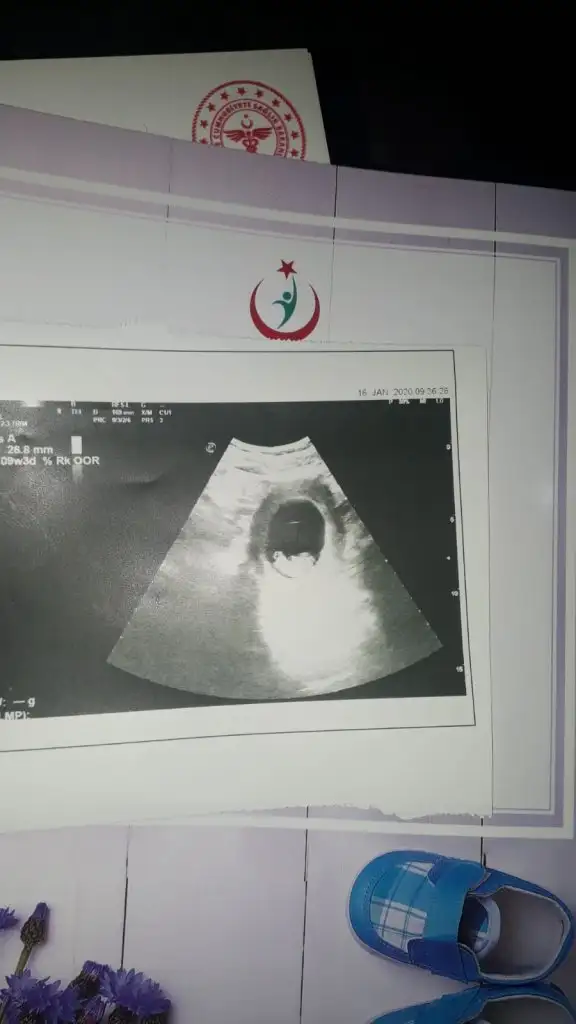

Arkadaşlar merhaba. Bugün doktora gittim tam 8 haftalık. Ultrason fotoğrafına yorum yapabilir misiniz cinsiyet için?

Eklentiler

• 20200121_154342-1.webp

25,9 KB · Görüntüleme: 135